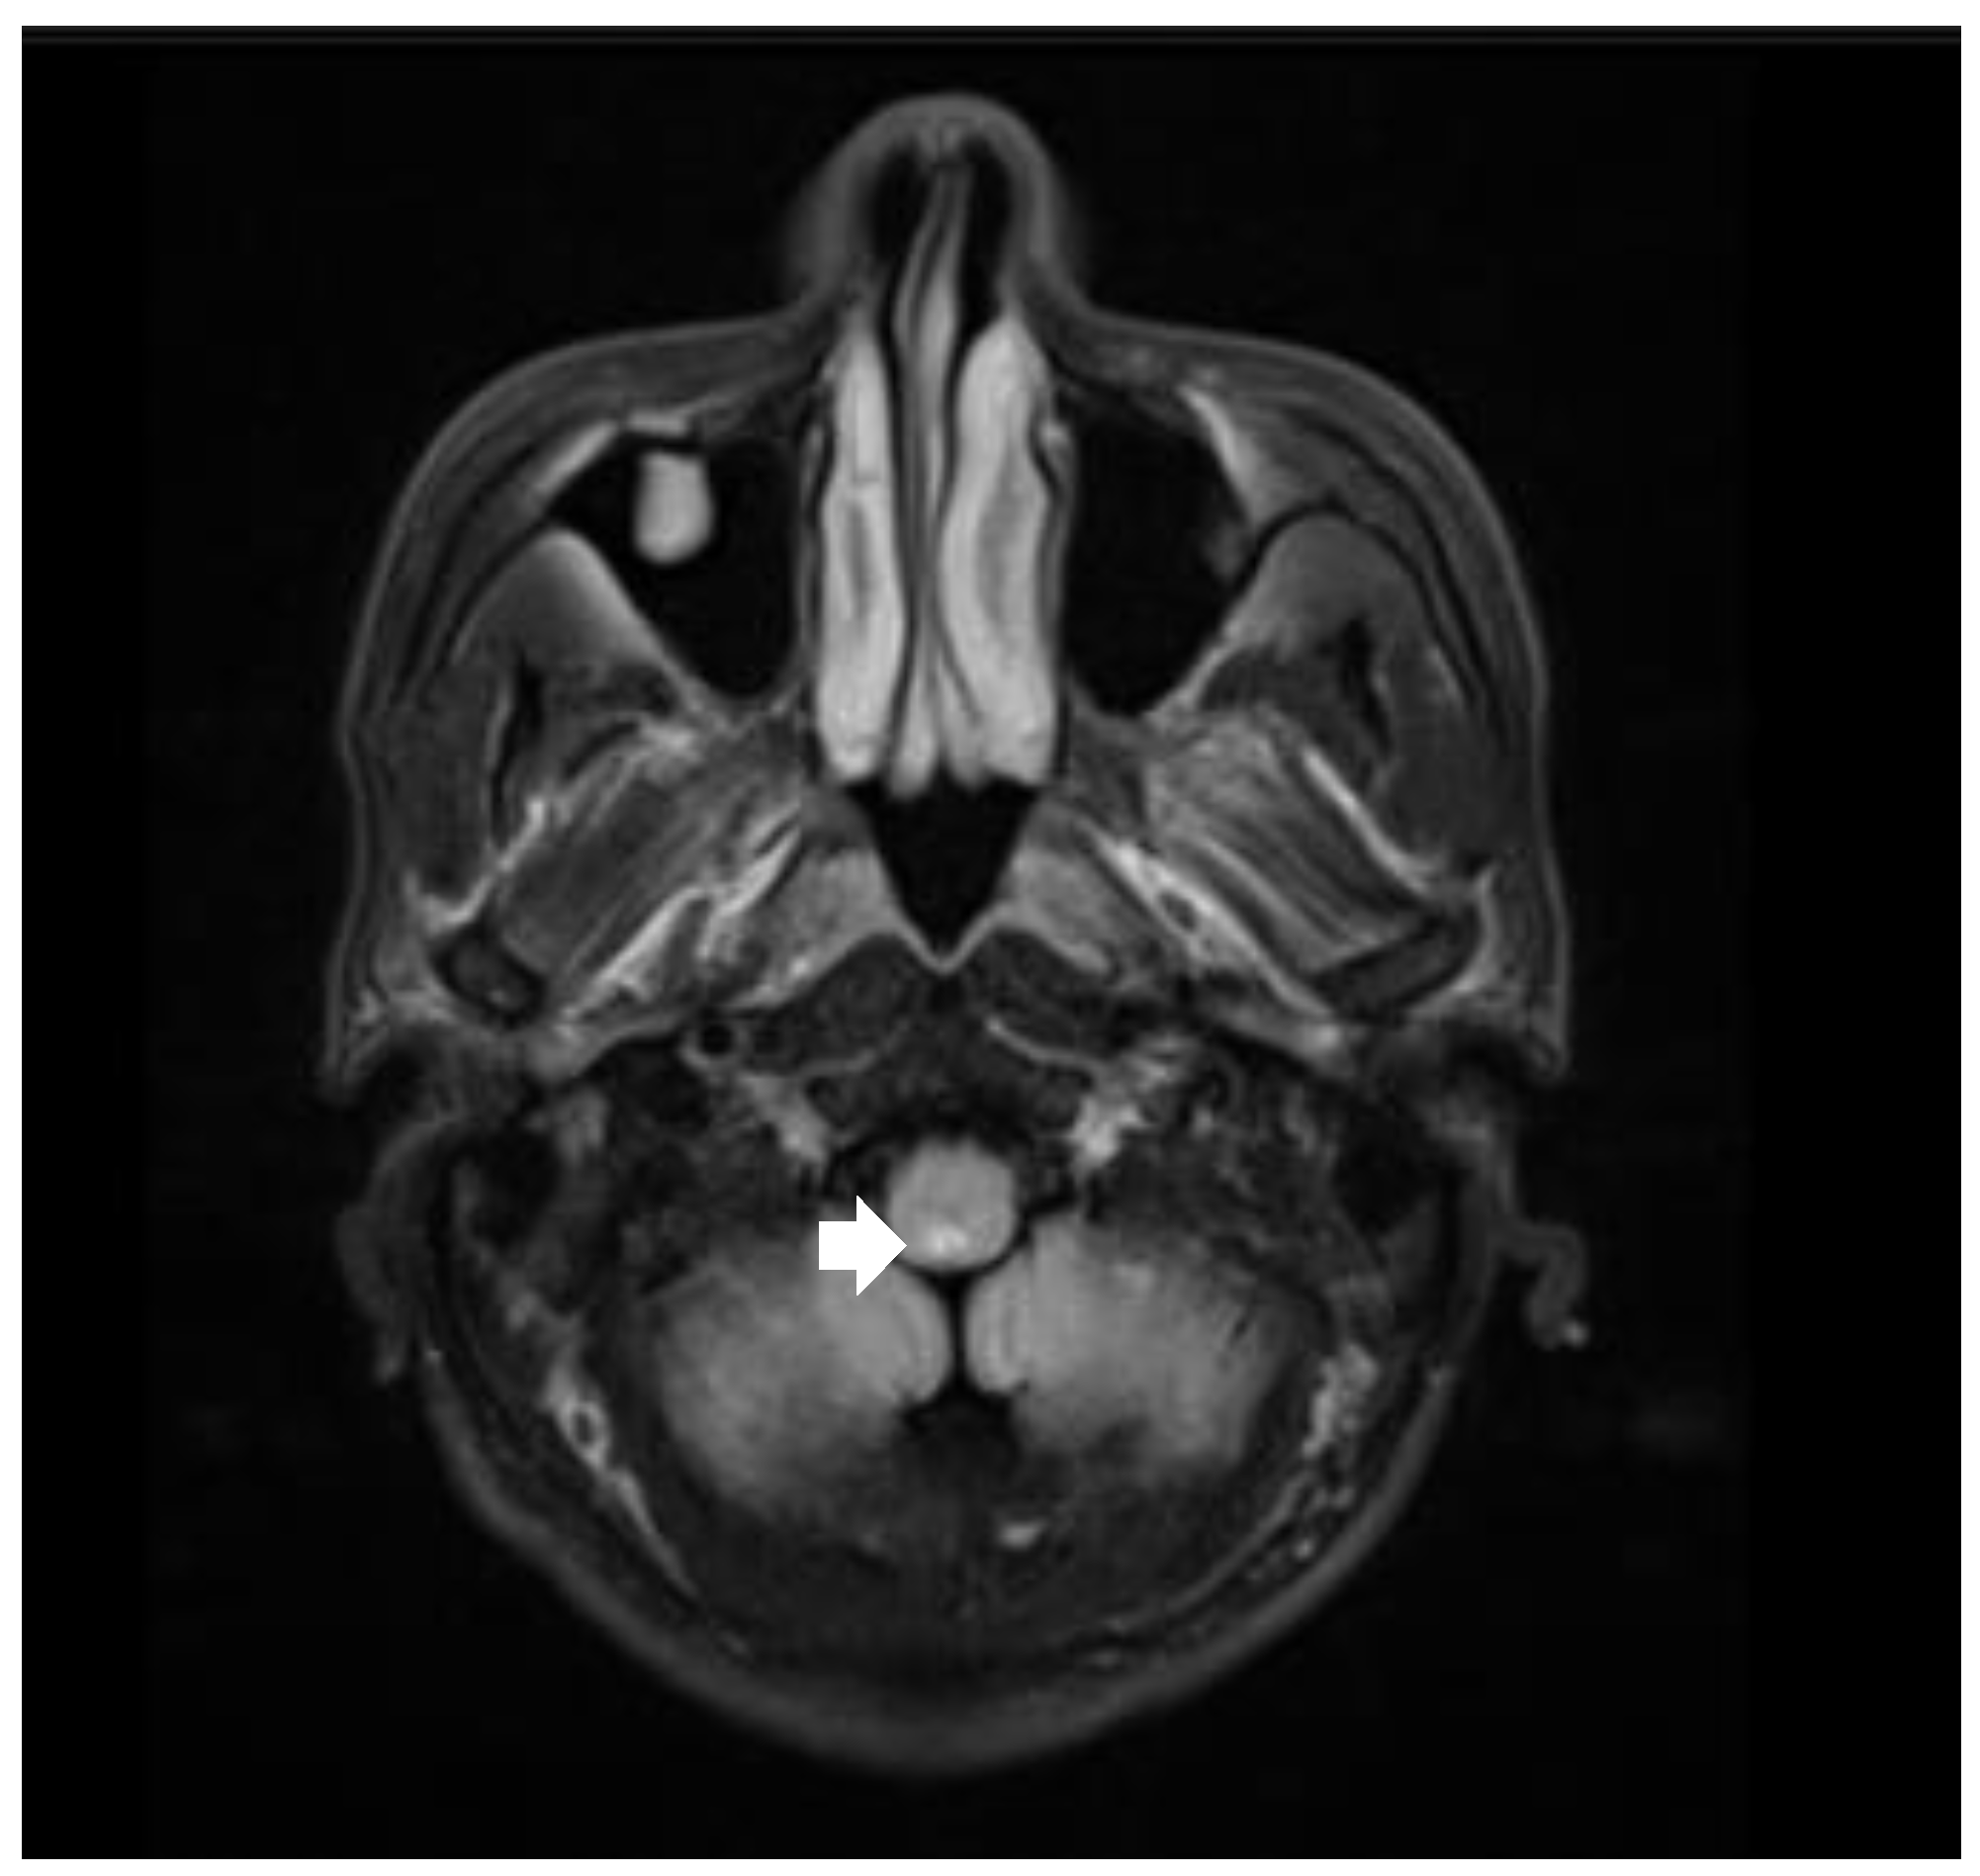

3.1. Case 1

| 9 | 45 | M | Sinus arrest | Syncope, APS | Medulla oblongata | No | IVMP, IVIG |

| 10 | 26 | M | Cardiac arrest | APS, limbs weakness, dysphagia, diplopia | Medulla oblongata, pons and mesencephalon | No | IVMP, PE, IVIG |